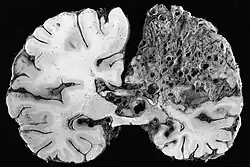

In serious cases, blood vessels rupture and cause bleeding within the brain (intracranial hemorrhage).[a] In more than half of patients with AVM, this is the first symptom.[7] Symptoms due to bleeding include loss of consciousness, sudden and severe headache, nausea, vomiting, incontinence, and blurred vision, amongst others.[4] Impairments caused by local brain-tissue damage on the bleed site are also possible, including seizure, one-sided weakness (hemiparesis), a loss of touch sensation on one side of the body and deficits in language processing (aphasia).[4] Ruptured AVMs are responsible for considerable mortality and morbidity.[8]

The main risk is intracranial hemorrhage. This risk is difficult to quantify since many patients with asymptomatic AVMs will never come to medical attention. Small AVMs tend to bleed more often than do larger ones, the opposite of cerebral aneurysms.[29] If a rupture or bleeding incident occurs, the blood may penetrate either into the brain tissue (cerebral hemorrhage) or into the subarachnoid space, which is located between the sheaths (meninges) surrounding the brain (subarachnoid hemorrhage). Bleeding may also extend into the ventricular system (intraventricular hemorrhage). Cerebral hemorrhage appears to be most common.[3] One long-term study (mean follow up greater than 20 years) of over 150 symptomatic AVMs (either presenting with bleeding or seizures) found the risk of cerebral hemorrhage to be approximately 4% per year, slightly higher than the 2–4% seen in other studies.[30][6] The earlier an AVM appears, the more likely it is to cause hemorrhage over one's lifetime; e.g. (assuming a 3% annual risk), an AVM appearing at 25 years of age indicates a 79% lifetime chance of hemorrhage, while one appearing at age 85 indicates only a 17% chance.[6] Ruptured AVMs are a significant source of morbidity and mortality; following a rupture, as many as 29% of patients will die, with only 55% able to live independently.[8]